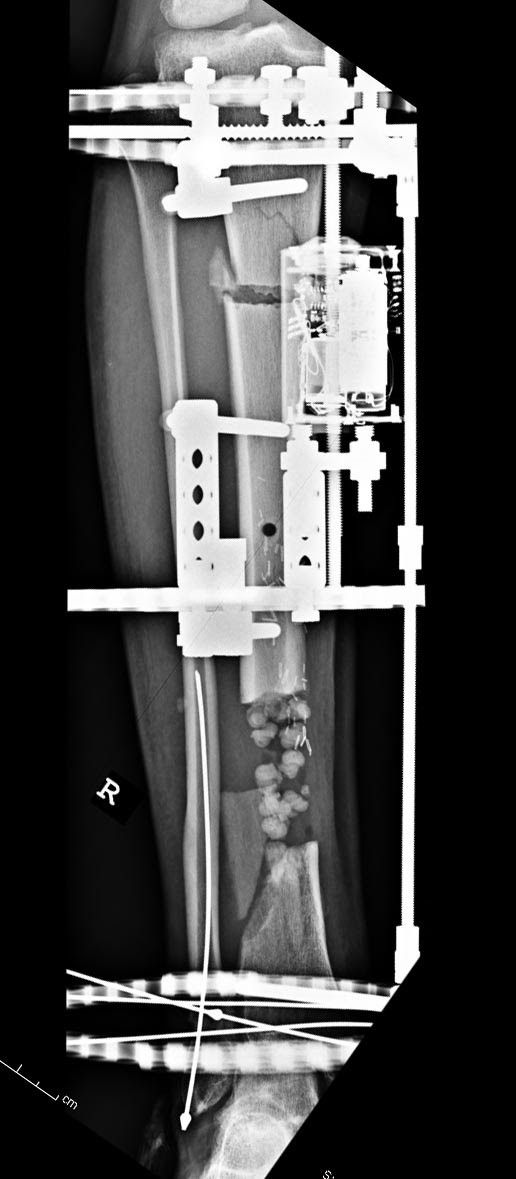

Данный случай не огнестрельная рана, а результат мотоциклетной аварии. Независимо от повреждения при таких обширных дефектах мягких и костной тканей применяется схожая тактика. Как видно, после нескольких I&D для создания “pseudo membrane” применили цилиндрический блок из цемента. Дефект мягких тканей закрыли свободным Anterior Thigh Graft. Из малого доступа цилиндр удален небольшими кусочками, а пространство заполнили бусами для освобождения пространства. По мере приближения регенерата освободили пространство удалением бус через небольшой разрез. Этап созревание регенерата можно было ускорить усилением интрамедуллярным гвоздем, но решили закончить методом Илизарова.

Теперь по поводу данного случая - “спейсер” из цемента предупреждает инфекцию и сохраняет пространство. Но вместо “бус” “цилиндрическая форма” более удобная, вокруг нее образуется ровная трубчатая поверхность “псевдо-мембраны” что в дальнейшей позволит закрыть небольшие дефекты “графтом” или во время удлинения облегчает скольжение регенерата как по трубке.

Из истории Афганской войны известно, что "доктрина убирать все фрагменты с последующим замещением дефекта" привела к долгим восстановительным операциям. А проведенные работы в США в начале 90х по фиксации огнестрельных переломов показали, что классические методы фиксации гвоздем намного лучше, чем сложные восстановительные операции. Чем быстрее создается стабильность, тем лучше, и при сохранении длины костей переломы срастаются в те же сроки и с очень низким процентом осложнений.